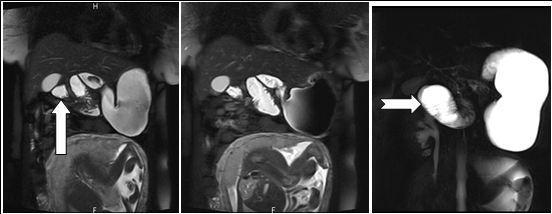

Figure 2B.Axial contrast-enhanced MRI scans show characteristic whirpool appearance of bowel and mesentery wrapping around superior mesenteric artery

Axial contrast-enhanced MRI scans show characteristic whirpool appearance of bowel and mesentery wrapping around superior mesenteric artery

Figure 3.Coronal reformatted image shows contrast agent–filled small bowel on right

Coronal reformatted image shows contrast agent–filled small bowel on right

A 28 weeks and 4 days pregnant, 29 years-old female, known for an L4-L5 discopathy and a past history of surgery for appendicitis at the age of 10 (right-positioned appendix, not perforated), consulted with vomiting and abdominal pain in the epigastric region. Eating and drinking had become impossible at that point. Blood tests revealed pathologically elevated white blood cells count (11.4 G/l for a normal value of 4-10 G/l) and elevated hepatic tests. Preeclampsia and HELLP syndrome were ruled out, as were frequent causes for hepatitis (virus, medicines, auto-immunity). Abdominal echography did not reveal any sign of cholecystitis or pancreatitis and testing for urinary cause was negative. The second blood tests revealed a worsening of the hepatic tests, reason why the patient underwent a cholangio-MRI. This test did not reveal any biliary lesion but volvulus was suspected due to apparent intestinal malrotation. Obtruction was confirmed by gastroscopy (without scope) and situated at the level of the jejunum. Final confirmation of obstruction and its position in the abdomen was also obtained through intestinal MRI (see Figure 2A, Figure 2B, Figure 3). During this time, the patient never displayed any gynaecological signs and foetal echography revealed a foetus with cephalic position, weighting 1300g and a posteriorly inserted healthy placenta with a Manning score of 10/10. The patient was referred for surgery. She underwent an exploratory laparoscopy that revealed multiple adhesions of the small intestine. Volvulus of the small intestine was identified just at the level of the duodeno-jejunal angle, situated on the right side of the aorta. Removal of the adhesions was attempted but ended up causing a small lesion of the small intestine, prompting the transformation of the laparoscopy into an open laparotomy. The laparotomy revealed a volvulus of the small intestine with common mesentery, with encircling of the caecum, the last part of the ileum and the beginning of the jejunum by the omentum. Resolution of the volvulus showed absence of intestinal rotation at the duodeno-jejunal angle, confirming the presence of malrotation. Mesentery was repositioned (without Ladd’s procedure) and fixation of the right colon to the right peritoneum was performed. The small intestine, which showed no sign of ischemia, was sutured and adhesions were completely removed. A few hours after the surgery, the patient presented with uterine contractions every two minutes and uterine ultrasonography showed a 33mm cervix. Tocolysis was immediately given with good results and the contractions definitely ceased and did not reappear two days later when treatment was stopped. During her stay, the patient presented with left basal pneumonia that was treated with antibiotherapy. She completely recovered during the following days and was then discharged with no further complication. The rest of her pregnancy went without any other complication and the patient delivered with instrumentation (Kiwi-sucker) at the age of 40 weeks and 0 days due to a suspect cardio-tocogramm and absence of delivery progression. Both baby and mother were healthy and they were then discharged with no further complication

In that aspect, small bowel volvulus should always remain in the differential diagnosis in front of a pregnant woman presenting with abdominal pain during pregnancy, especially one like ours that was known for a previous surgery for appendicitis (a possible reason for the presence of the adhesions). Radiologic diagnosis of small bowel volvulus can be done by several technics. Plain abdominal film can be used, showing sometimes a typical pattern of dilated loops, but more often showing a normal radiological pattern due to a proximal position of the volvulus (with the loops being filled with liquid). Evidences on CT-scan are the presence of dilated bowel loops, intramural gas and the “whirlpool sign” (Cong et al, 2014; Shui et al, 2011)4, 12, but the use of technics exposing the foetus to radiations is debated. However, in their review, Cong et al 4emphasized the fact that those technics (and particularly plain radiography) are considered safe for the mother as well as for the foetus (Cong et al, 2014)4. MRI is also safe and extremely precise in the diagnosis of small bowel obstruction (Vassiliou et al, 2012)13, sometimes also showing the “whirlpool sign” (Kouki et al, 2013)7 and ultrasonography has been reported to be useful in some instances (Cong et al, 2014)4 but it can also remain completely negative. In our case, while cholangio-MRI suggested the diagnosis, final diagnosis was given by intestinal MRI, showing a possible role for this technic in some unusual cases, in which doubts about the diagnosis or about the state of different abdominal structures remain. However, in cases in which clinical symptoms, laboratory and more basic radiological (plain abdominal film of CT-scan) are highly suggestive of this pathology, exploratory surgery should be started at the earliest time possible.